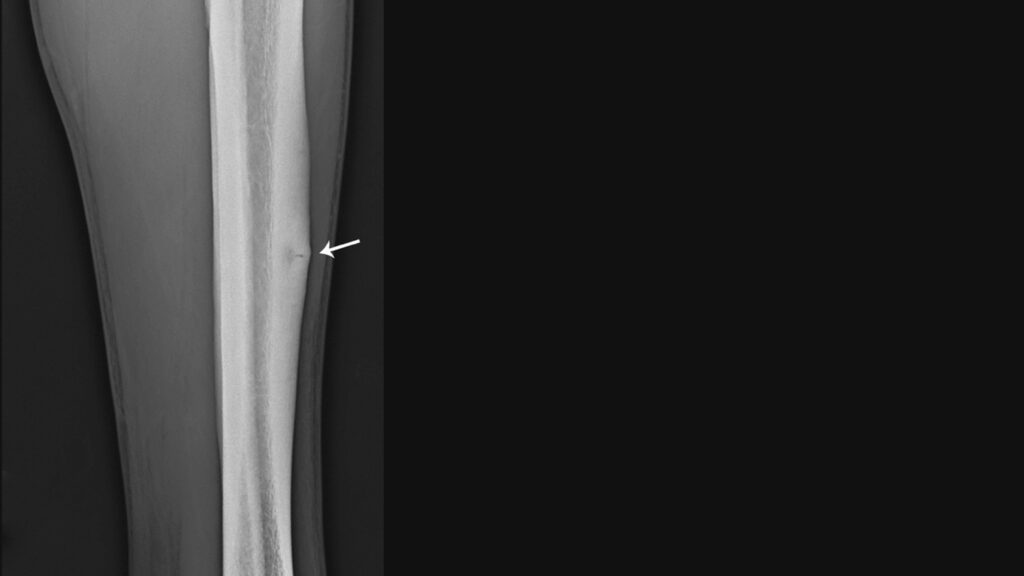

疲労骨折との違い

シンスプリントのほかにもスポーツに伴ってすねの内側が痛くなるケガのひとつに、疲労骨折があります。痛む箇所もよく似ていていますが、治療方法が異なるので正確な判断が求められます。

シンスプリントの場合、痛みを感じる部分が約10cmと長く、半数近くは両足のすねに症状が出るのが特徴です。また、徐々に発生する下腿内側(主に脛骨内縁中1/3、目安として脛骨内踝より12~20cm上)の圧痛、運動時痛、腫張が主症状で、足屈筋の抵抗運動で痛みは増強します。

一方、疲労骨折の場合は、片方のみに発症するケースがほとんどで、5cm以下のピンポイントで痛みが発生します。